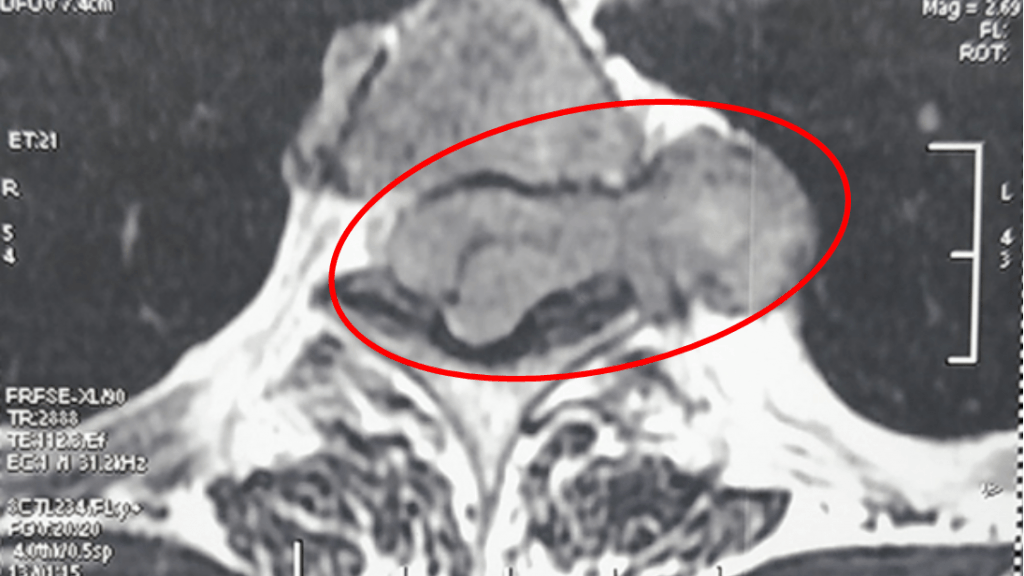

Пациент жаловался на слабость и боли в нижней конечности. По результатам магнитно-резонансной томографии грудного отдела позвоночника у него было диагностировано большое новообразование на уровне 2-4 грудных позвонков, прорастающее в грудную клетку.

Нейрохирурги с помощью нового операционного микроскопа новой эргоконцепции своевременно провели успешное оперативное вмешательство пациенту - ламиноэктомию с микрохирургическим удалением опухоли. Малый объём оперативного доступа и минимальная кровопотеря при операции позволят пациенту уже в ближайшее время вернуться к полноценной жизни, сообщили в Минздраве региона.